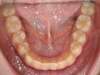

Cas 3 : Description

Encombrement aux deux arcades.Traitement par gouttières.

Avant

Après